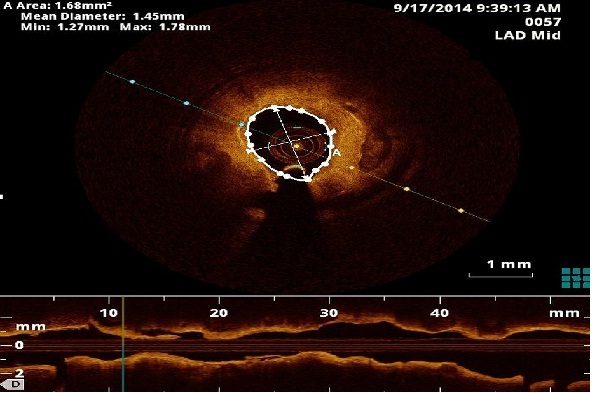

Qual a localização das zonas de um vaso sanguíneo com maior risco de reestenose após a aplicação de um stent farmacológico? Sirolimus ou Paclitaxel, qual o mais eficaz? Qual a posição do stent farmacológico com melhores resultados?

Estas são algumas das questões colocadas em cardiologia para as quais a matemática pode contribuir na procura de respostas.